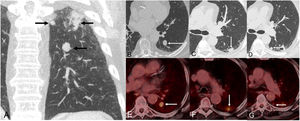

The patient was a 72-year-old male, active smoker, who complained of progressive dyspnea and cough. A chest radiograph showed a nodular opacity in the left lung, so it was decided to perform a thoracic CT, which confirmed the presence of 3 suspicious lesions in the superior segment of the left lower lobe (Fig. 1A): one 16-mm solid nodule in the inferior aspect of the superior segment (lesion 1, Fig. 1B), one 17-mm solid subpleural nodule in the superior and lateral aspect of the superior segment (lesion 2, Fig. 1C), and one 11-mm solid subpleural nodule in the superior and medial aspect of the inferior segment (lesion 3, Fig. 1D). Fluorine-18 fluorodeoxyglucose positron emission tomography/CT (FDG-PET/CT) demonstrated variable standardized uptake values (SUVs) by the three lung nodules: SUV of 4.7 (lesion 1, Fig. 1E), SUV of 4.3 (lesion 2, Fig. 1F), and SUV of 2.2 (lesion 3, Fig. 1G), suggesting a different glycolytic metabolism. There were no signs of mediastinal or distant metastases. Endobronchial ultrasound (EBUS) and bronchial brushing did not show malignant cells. A presumed diagnosis of a T3 (lung cancer associated with ipsilobar nodules) tumor was made, and the patient underwent a video-assisted thoracoscopic left lower lobectomy. Pathologic findings revealed a low-grade malignant neuroendocrine tumor (pT1bN0M0, lesion 1), an invasive acinar-predominant adenocarcinoma (pT1bN0M0, lesion 2), and another invasive acinar-predominant adenocarcinoma (pT1bN0M0). Although the microscopic morphology of lesions 2 and 3 were similar, immunohistochemical differences (Table 1) confirmed that they represented two independent primary lung adenocarcinomas.

(A) Coronal CT image (lung window) shows 3 suspicious lung nodules in the superior segment of the left lower lobe. (B) Axial CT image (lung window) shows one solid nodule in the inferior region of the superior segment (arrow, lesion 1). (C) Axial CT image (lung window) shows one subpleural nodular opacity in the lateral aspect of the superior segment (arrow, lesion 2). (D) Axial CT image (lung window) shows one small solid nodule in the medial aspect of the superior segment (arrow, lesion 3). (E–G) Axial fused PET/CT images corresponding to lesions shown on Figs. B, C, and D, respectively.